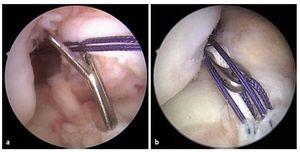

Fig. 11 La guía se extrae y se controla la posición del agujero remanente insertando el artroscopio dentro de la articulación a través del portal medial. Línea negra: línea intercondílea; línea punteada negra: interfaz huesocartílago; línea punteada roja: zona de inserción. AM: inserción del haz AM; PL: inserción del haz PL.

Fig. 15 a) La imagen muestra la posición del túnel femoral en el centro de la inserción femoral. b) A través del portal medial se controla la posición del túnel femoral. Línea punteada negra: interfaz hueso-cartílago; línea punteada blanca: línea intercondílea; línea punteada roja: inserción del LCA; línea punteada azul: interfaz hueso-cartílago. AM: inserción del haz AM; PL: inserción del haz PL.

Los errores en el posicionamiento femoral se pueden evitar mediante la técnica de perforación a través de portal3. Varios estudios han revelado que es posible conseguir antes una posición anatómica del túnel a través del portal medial que mediante la técnica de perforación transtibial6,10,12,15,16. Así mismo, un estudio biomecánico mostró que los túneles perforados mediante la técnica de perforación a través de portal ofrecían una mejor estabilización frente al fenómeno de «pivot-shift» que las técnicas de perforación transtibiales3. Estos resultados se confirmaron clínicamente. Alentorn-Geli et al.1 han comparado pacientes sometidos a un reemplazo de LCA realizado mediante la técnica de perforación a través de portal con pacientes que fueron intervenidos mediante la técnica de perforación transtibial y mostraron que los pacientes intervenidos con la técnica de perforación a través de portal pudieron volver antes a entrenar y a practicar deporte. La estabilidad a.-p. (KT 1000), así como la estabilidad rotatoria, eran significativamente mejores en el grupo de pacientes operados con la técnica de perforación a través de portal. Otra ventaja de la técnica de perforación a través de portal es la menor incidencia de casos de ensanchamiento de túnel5. A pesar de realizar la técnica de perforación a través de portal medial, siempre se debería controlar la posición del alambre femoral durante la intervención. Dado que la visibilidad sobre el cóndilo femoral lateral es insuficiente, el artroscopio se tiene que introducir en la articulación a través del portal medial13. El portal medial (ángulo visual desde el portal medial) ofrece una visibilidad mucho mejor sobre el cóndilo femoral lateral que el portal lateral13. Las alternativas para el control de la posición del alambre son el fluoroscopio y la navegación.

La línea intercondílea y la interfaz hueso-cartílago sirven como puntos de referencia13, fig. 4a). En el reemplazo de LCA total, el centro del túnel debe estar en el centro de la inserción femoral9.